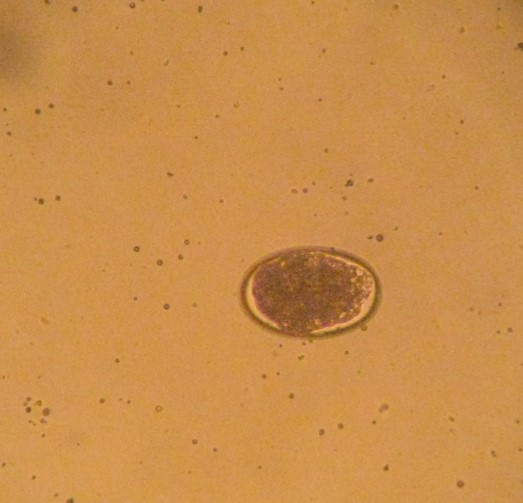

Histomonas

Histomonas meleagridis : protozoaire flagellé responsable de la maladie de la tête noire chez les poules. Il est généralement transmis par les vers de type Heterakis gallinarum et cause de graves lésions nécrosantes du foie et des caeca (typhlite nécrosante et pseudomembraneuse). La survie du parasite est limitée dans le milieu extérieur. La maladie se déclare surtout chez le dindon et le paon, la poule est plus résistante.